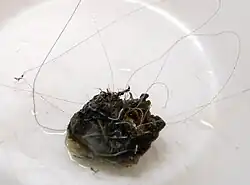

O tratamento utiliza molas destacáveis feitas de platina, que são inseridas no aneurisma usando o microcateter. Existe uma variedade de molas, incluindo as molas destacáveis de Guglielmi (GDC), que são malhas de platina revestidas com um biopolímero e hidrogel. Essas micro-molas também estão disponíveis em uma variedade de diâmetros, comprimentos e secções transversais.[12] Uma mola é inserida primeiramente ao longo da parede do aneurisma para criar um quadro, com o núcleo sendo preenchido com mais bobinas. Uma série de molas progressivamente menores também podem ser usadas. O sucesso é determinado pela injeção de contraste na artéria-mãe e qualitativamente determinando se o corante está fluindo no espaço do aneurisma durante a fluoroscopia. Se nenhum fluxo for observado, o procedimento é considerado finalizado.

Em 1983, o uso de trombose induzida por eletricidade foi descrita pela primeira vez.[6] Um eletrodo de aço inoxidável fornece uma corrente positiva ao aneurisma para estimular eletrotrombose. Uma oclusão mínima foi alcançada, mas os pesquisadores descobriram que a erosão do eletrodo devido à eletrólise seria útil como um sistema de desprendimento. As molas destacáveis foram construídas a partir de uma bobina de platina soldada a um fio de posicionamento de aço inoxidável, descritas pela primeira vez em 1991 por Guglielmi et al. Quando combinado com um sistema de fio de microguia controlável, várias molas podem ser inseridas para preencher completamente um aneurisma.